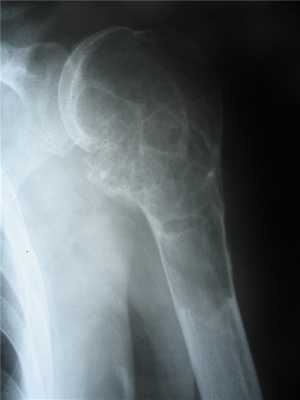

Клиническая картина. Боли и припухание в поражённых костях; мышечная слабость; патологические переломы; полидипсия, полиурия; иногда в течение многих лет протекает незаметно для больного. Рентгенологически отмечают распространенный остеопороз, расширение костномозгового канала длинных костей, субпериостальная деминерализация; пятнистый рисунок костей черепа, субпериостальная резорбции дистальных отделов ногтевых фаланг. Лабораторно обнаруживают повышение содержания в крови кальция, щелочной фосфатазы, паратгормона, снижение показателей фосфатов.

Макроскопически при длительном течении заболевания – деформации костей, подвергающихся наибольшей механической нагрузке (костей конечностей, позвоночника, грудной клетки). Кости становятся мягкими, иногда легко режутся ножом. Характерны множественные деформации в виде опухолевидных образований, наиболее часто встречающихся в длинных костях (чаще в диафизах), рёбрах, челюстях, имеющих на разрезе пестрый вид - желтовато-серые участки чередуются с темно-красными, бурыми («бурая опухоль» гиперпаратиреоза).

Микроскопия. Интенсивная перестройка костной ткани с усиленным остеокластическим рассасыванием кости; расширение хаверсовых каналов, спонгизация кортикального слоя, истончение костных трабекул; активная пролиферация фиброретикулярной ткани, формирование масс примитивной кости, наслаивающейся как на старые, так и на новые костные структуры; примитивная кость быстро подвергается резорбции и вновь замещается новообразованными костными массами.

«Бурая опухоль» представлена многочисленными многоядерными остеокластоподобными клетками, фибробластами, макрофагами, примитивными костными трабекулами, полями свежих и старых кровоизлияний, придающих поражению характерный вид.